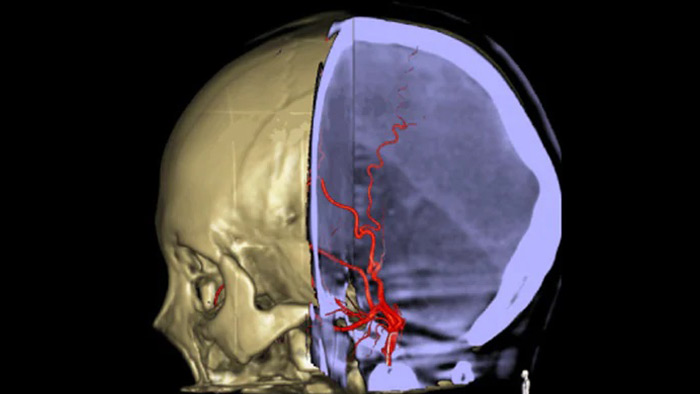

Las referencias anatómicas apoyan una navegación 3D precisa

SmartCT image

SmartCT Roadmap proporciona referencias anatómicas para apoyar la navegación precisa de la aguja guía, el catéter y el dispositivo al coágulo.